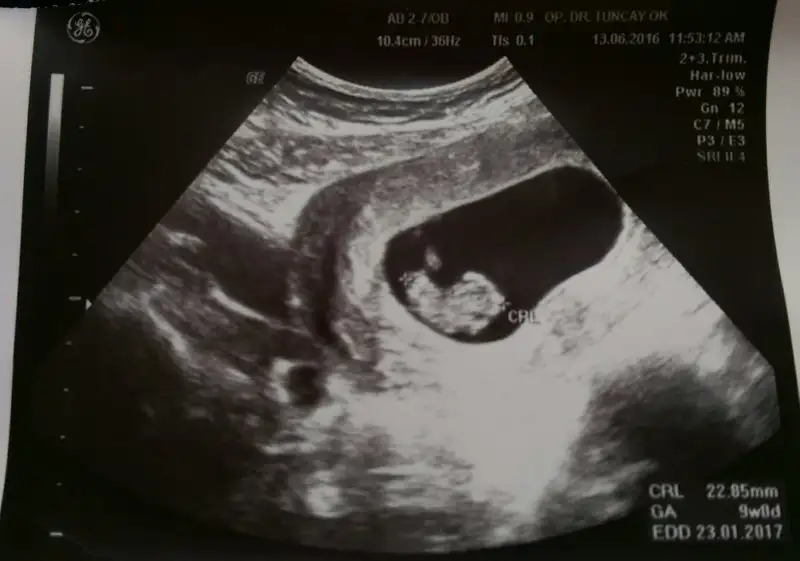

image.webp